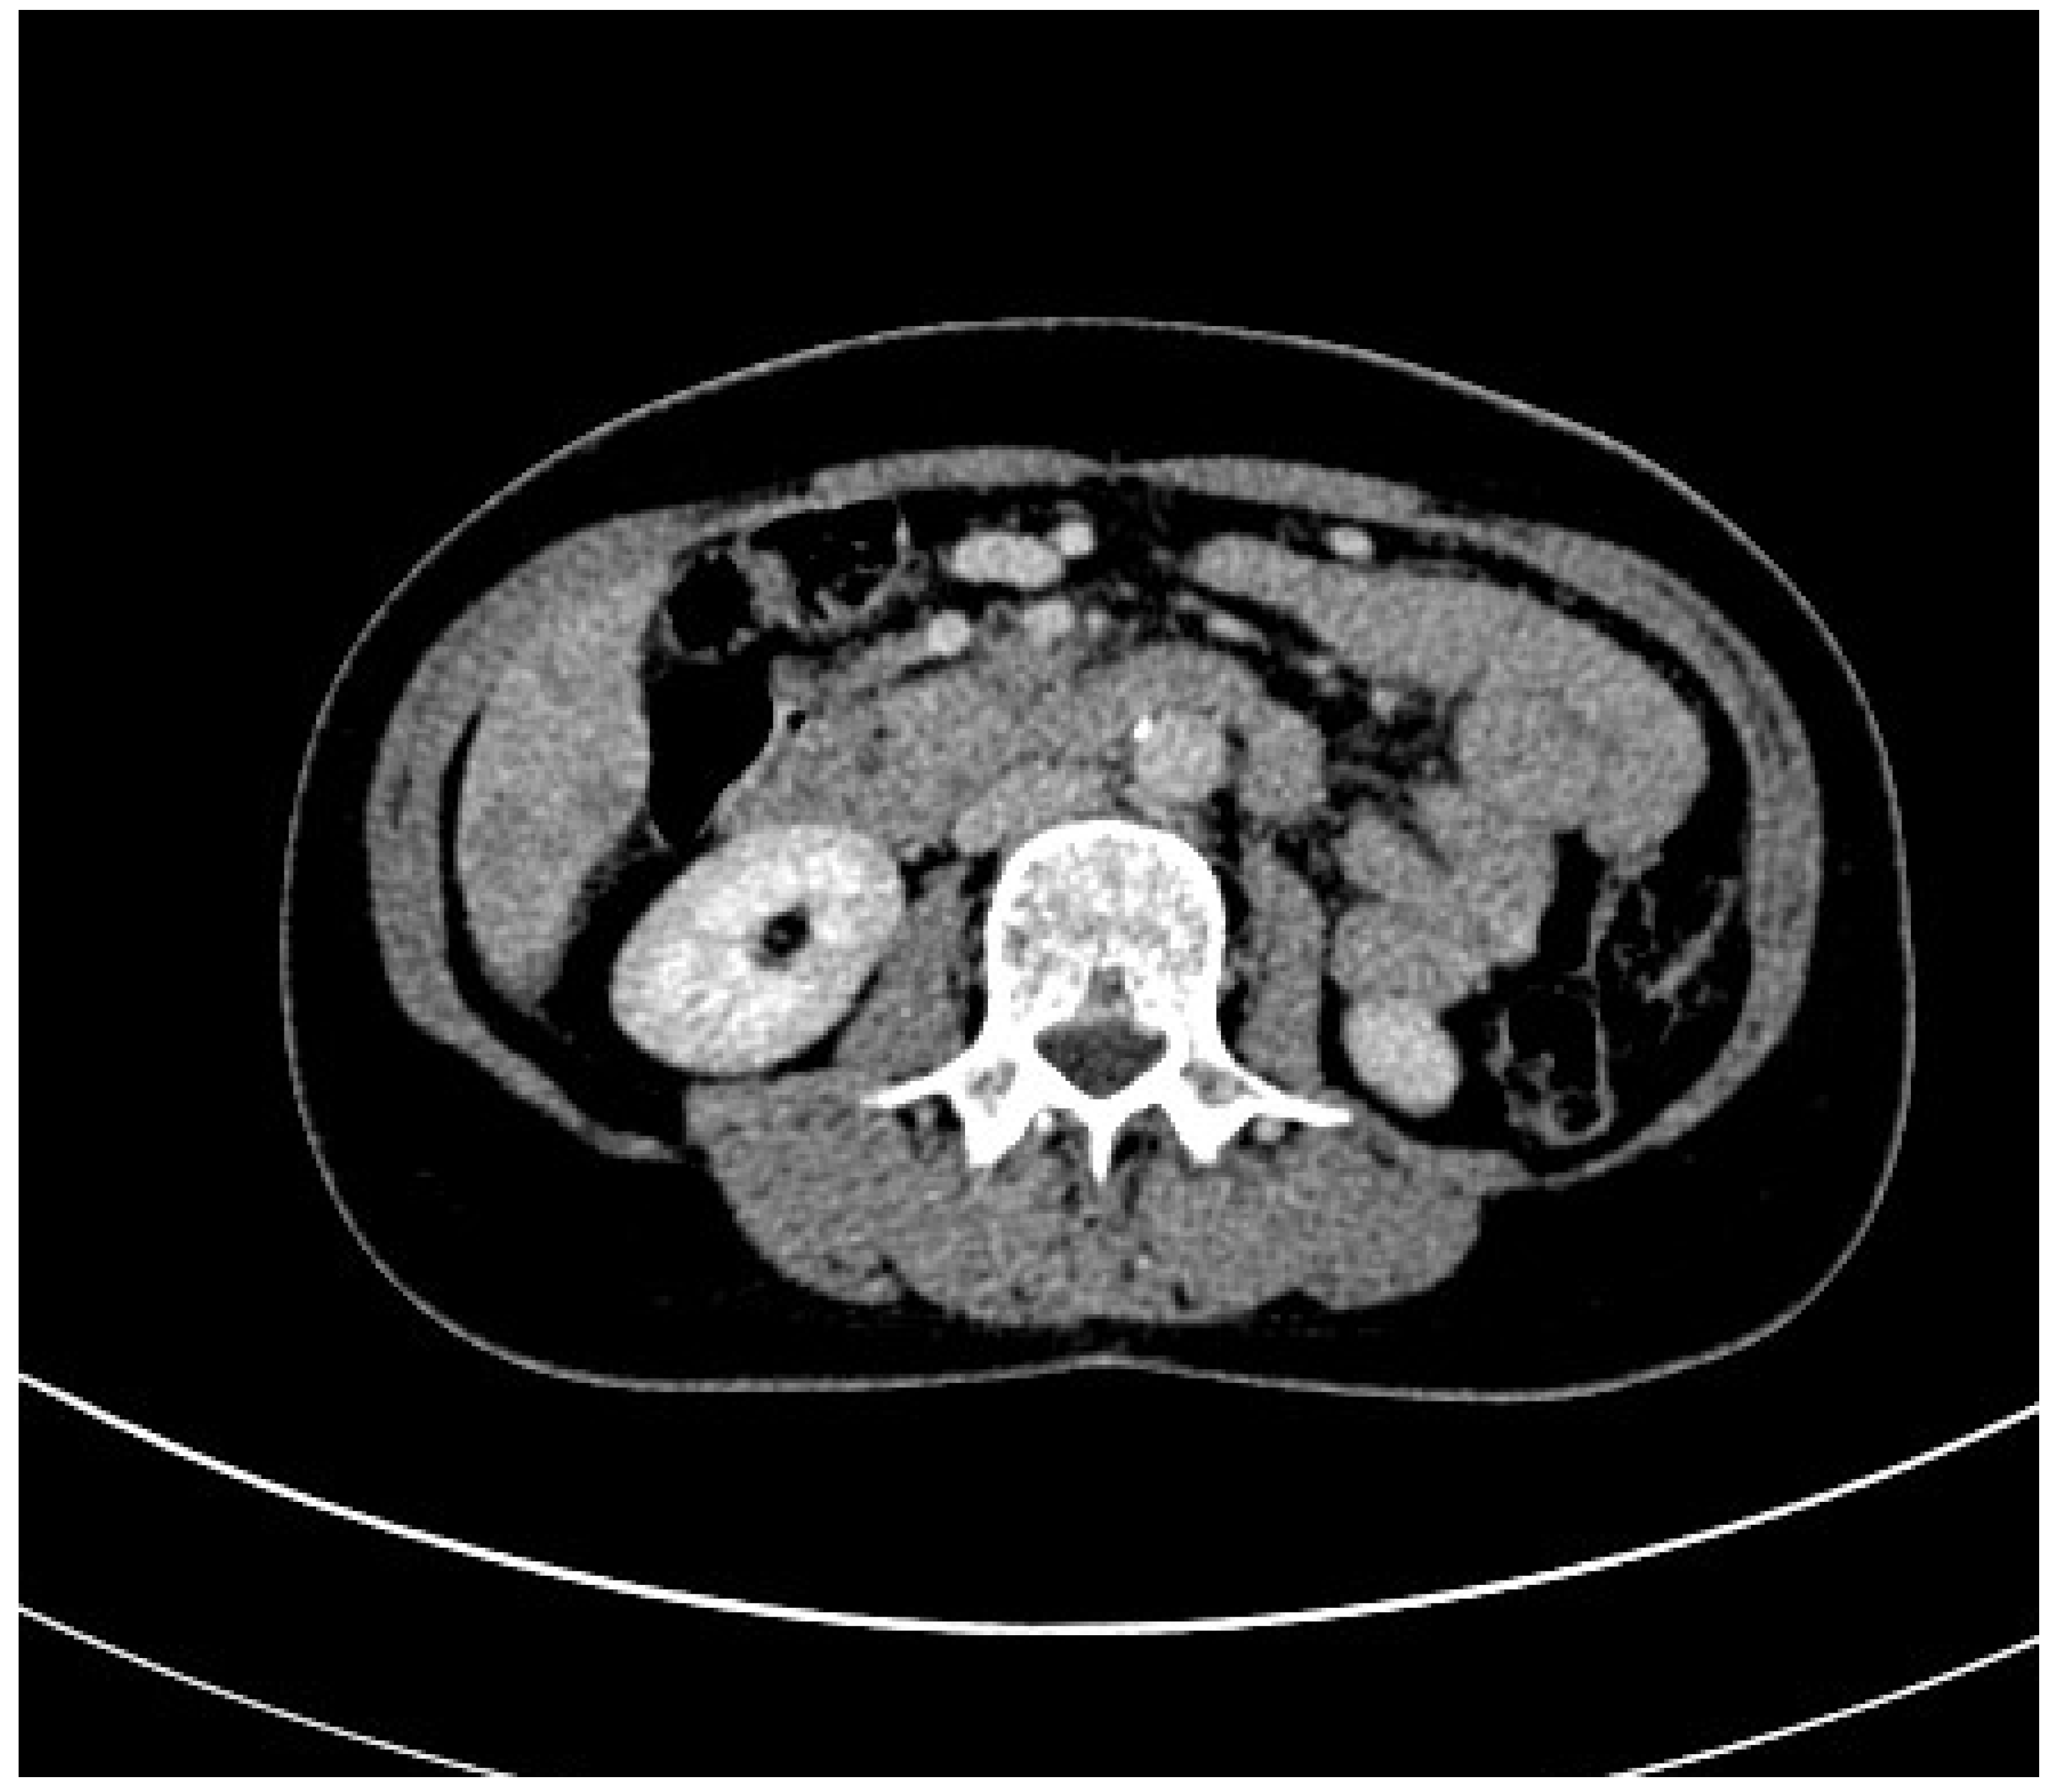

3.1. Computed Tomography